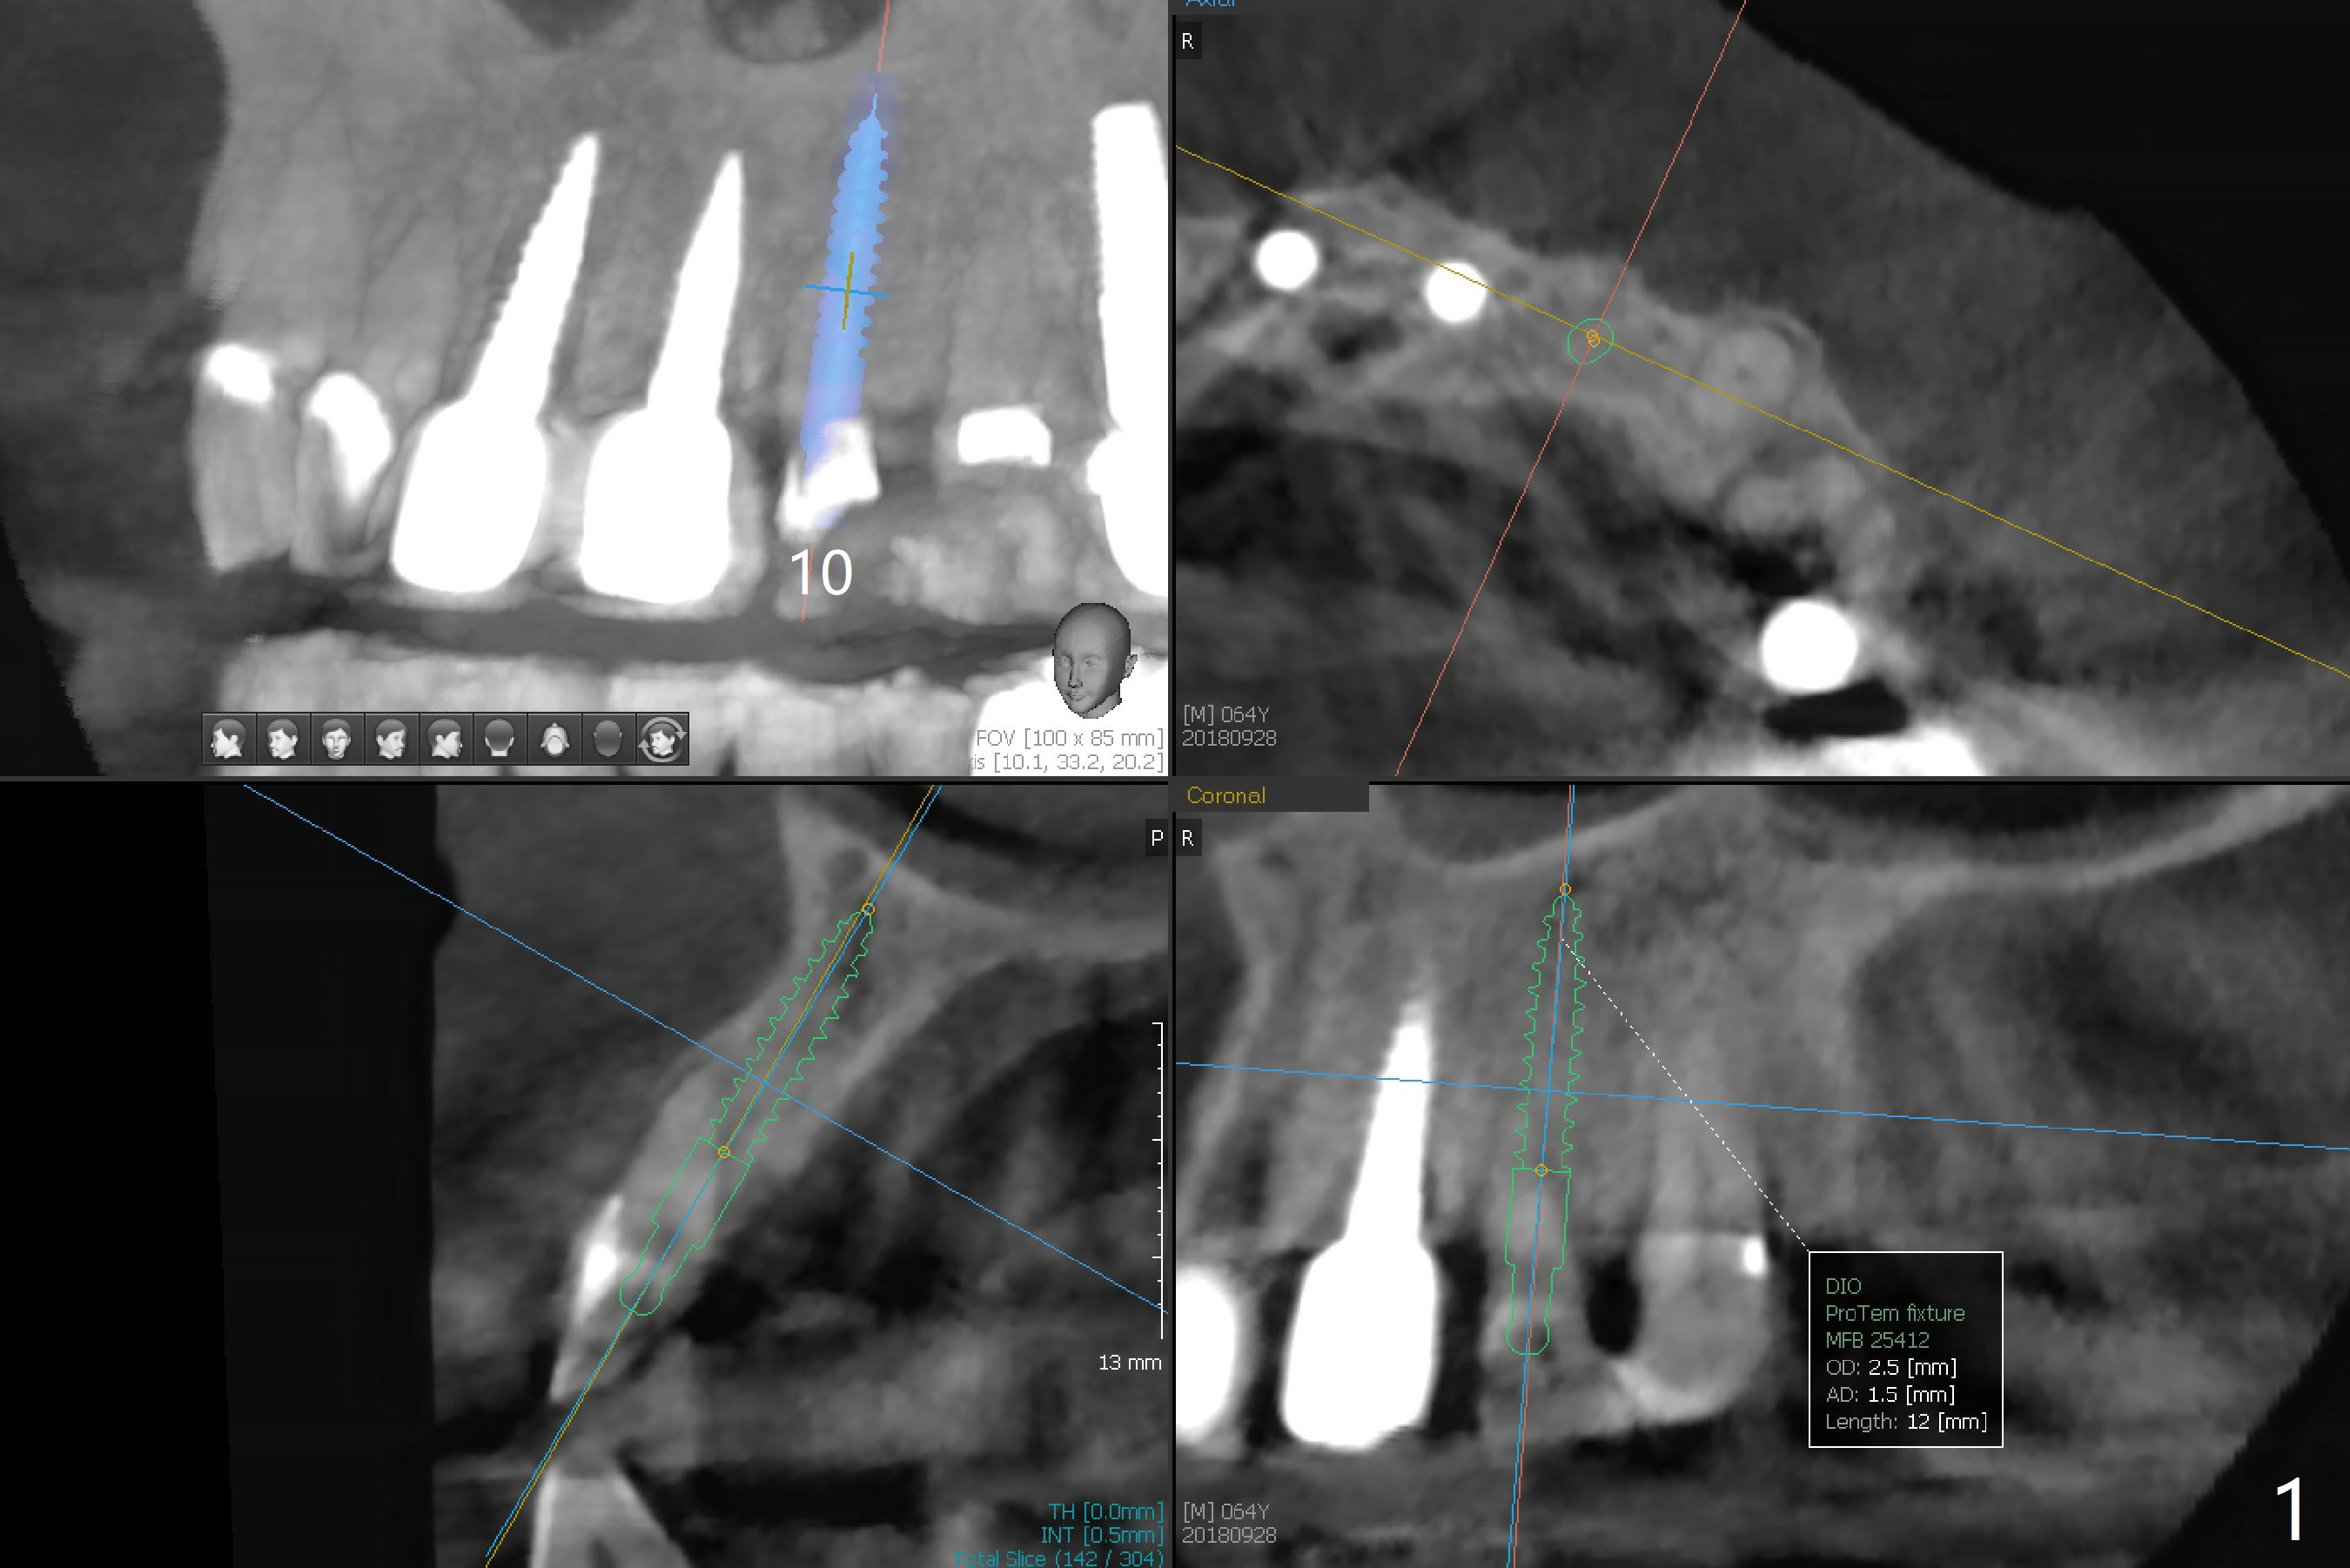

A 64-year-old man requests implant for the loose tooth at #10. The bone width is 5.5 mm (Fig.1); with 2.5 mm implant, there is 1.5 mm of the bone on the either side of the implant. The ideal width is 2 mm, which is safe, preventing buccal or palatal plate perforation. The buccal crest is lower when the tooth is extracted (Fig.4). Following trajectory confirmation (Fig.2), a 2.5x12(2) mm implant is placed a little deeper than expected to ensure no implant thread exposure with bone graft (Fig.3,5). The bone loss at #8 and 9 (Fig.2,3) is associated with the narrow ridge. The surface treatment of 1-piece implants is not as good as that of regular ones. The threads appears to be covered by the bone or bone graft 4 months postop (Fig.6).